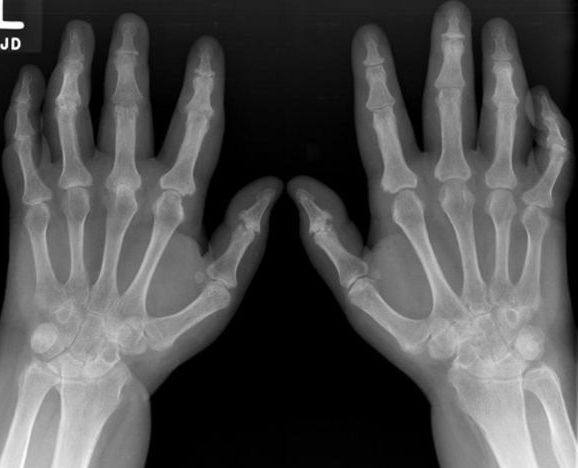

银屑病关节炎(PsA)是一种慢性炎症性疾病,会降低患者的活动能力和柔韧性...